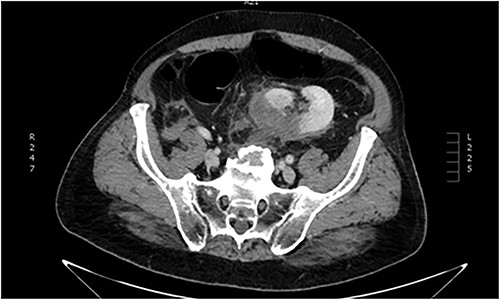

Imaging investigation with thoracic x-ray revealed 9th to 11th posterior rib fractures, as well as small pneumothorax on the right rib cage. Abdominal ultrasound revealed no internal bleeding or fluid within the peritoneal cavity and spaces, but an injured ectopic left kidney was detected within the pelvic cavity, previously unbeknownst to the patient. Further imaging with abdominal and pelvic computed tomography (CT) scan confirmed the occurrence of a grade III laceration (according to the American Association of the Surgery of Trauma—AAST renal injury grading scale) of the ectopic kidney (Figs. 1 and 2).

Abdominal CT imaging. Ectopic (pelvic) left kidney. Presence of grade III laceration without collecting system rupture or urinary extravagation.